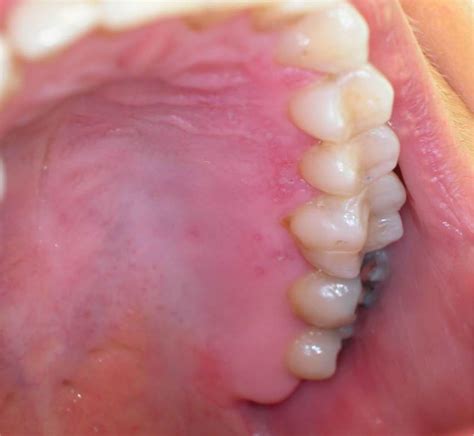

The virus responsible for oral outbreaks, Herpes Simplex Virus Type 1, is incredibly common. Once an individual is exposed, the virus typically remains dormant in the nerve ganglia, occasionally reactivating to cause lesions. While we often associate these lesions with the outer lip area, the virus can manifest as herpetic gingivostomatitis, a condition where the gums become inflamed, painful, and prone to bleeding. This is particularly common during a primary infection, which is the very first time the body encounters the virus.

In many cases, the interplay between herpes and gums is characterized by a sudden onset of symptoms. Unlike a standard canker sore, which usually appears as a single ulcer on the soft tissue inside the cheek, herpetic lesions often appear in clusters. When these clusters develop along the gumline, they can make routine hygiene like brushing extremely painful, leading to a temporary decline in oral health if not managed correctly.

• Small, fluid-filled blisters: These can rupture, forming small, painful ulcers on the gingiva.